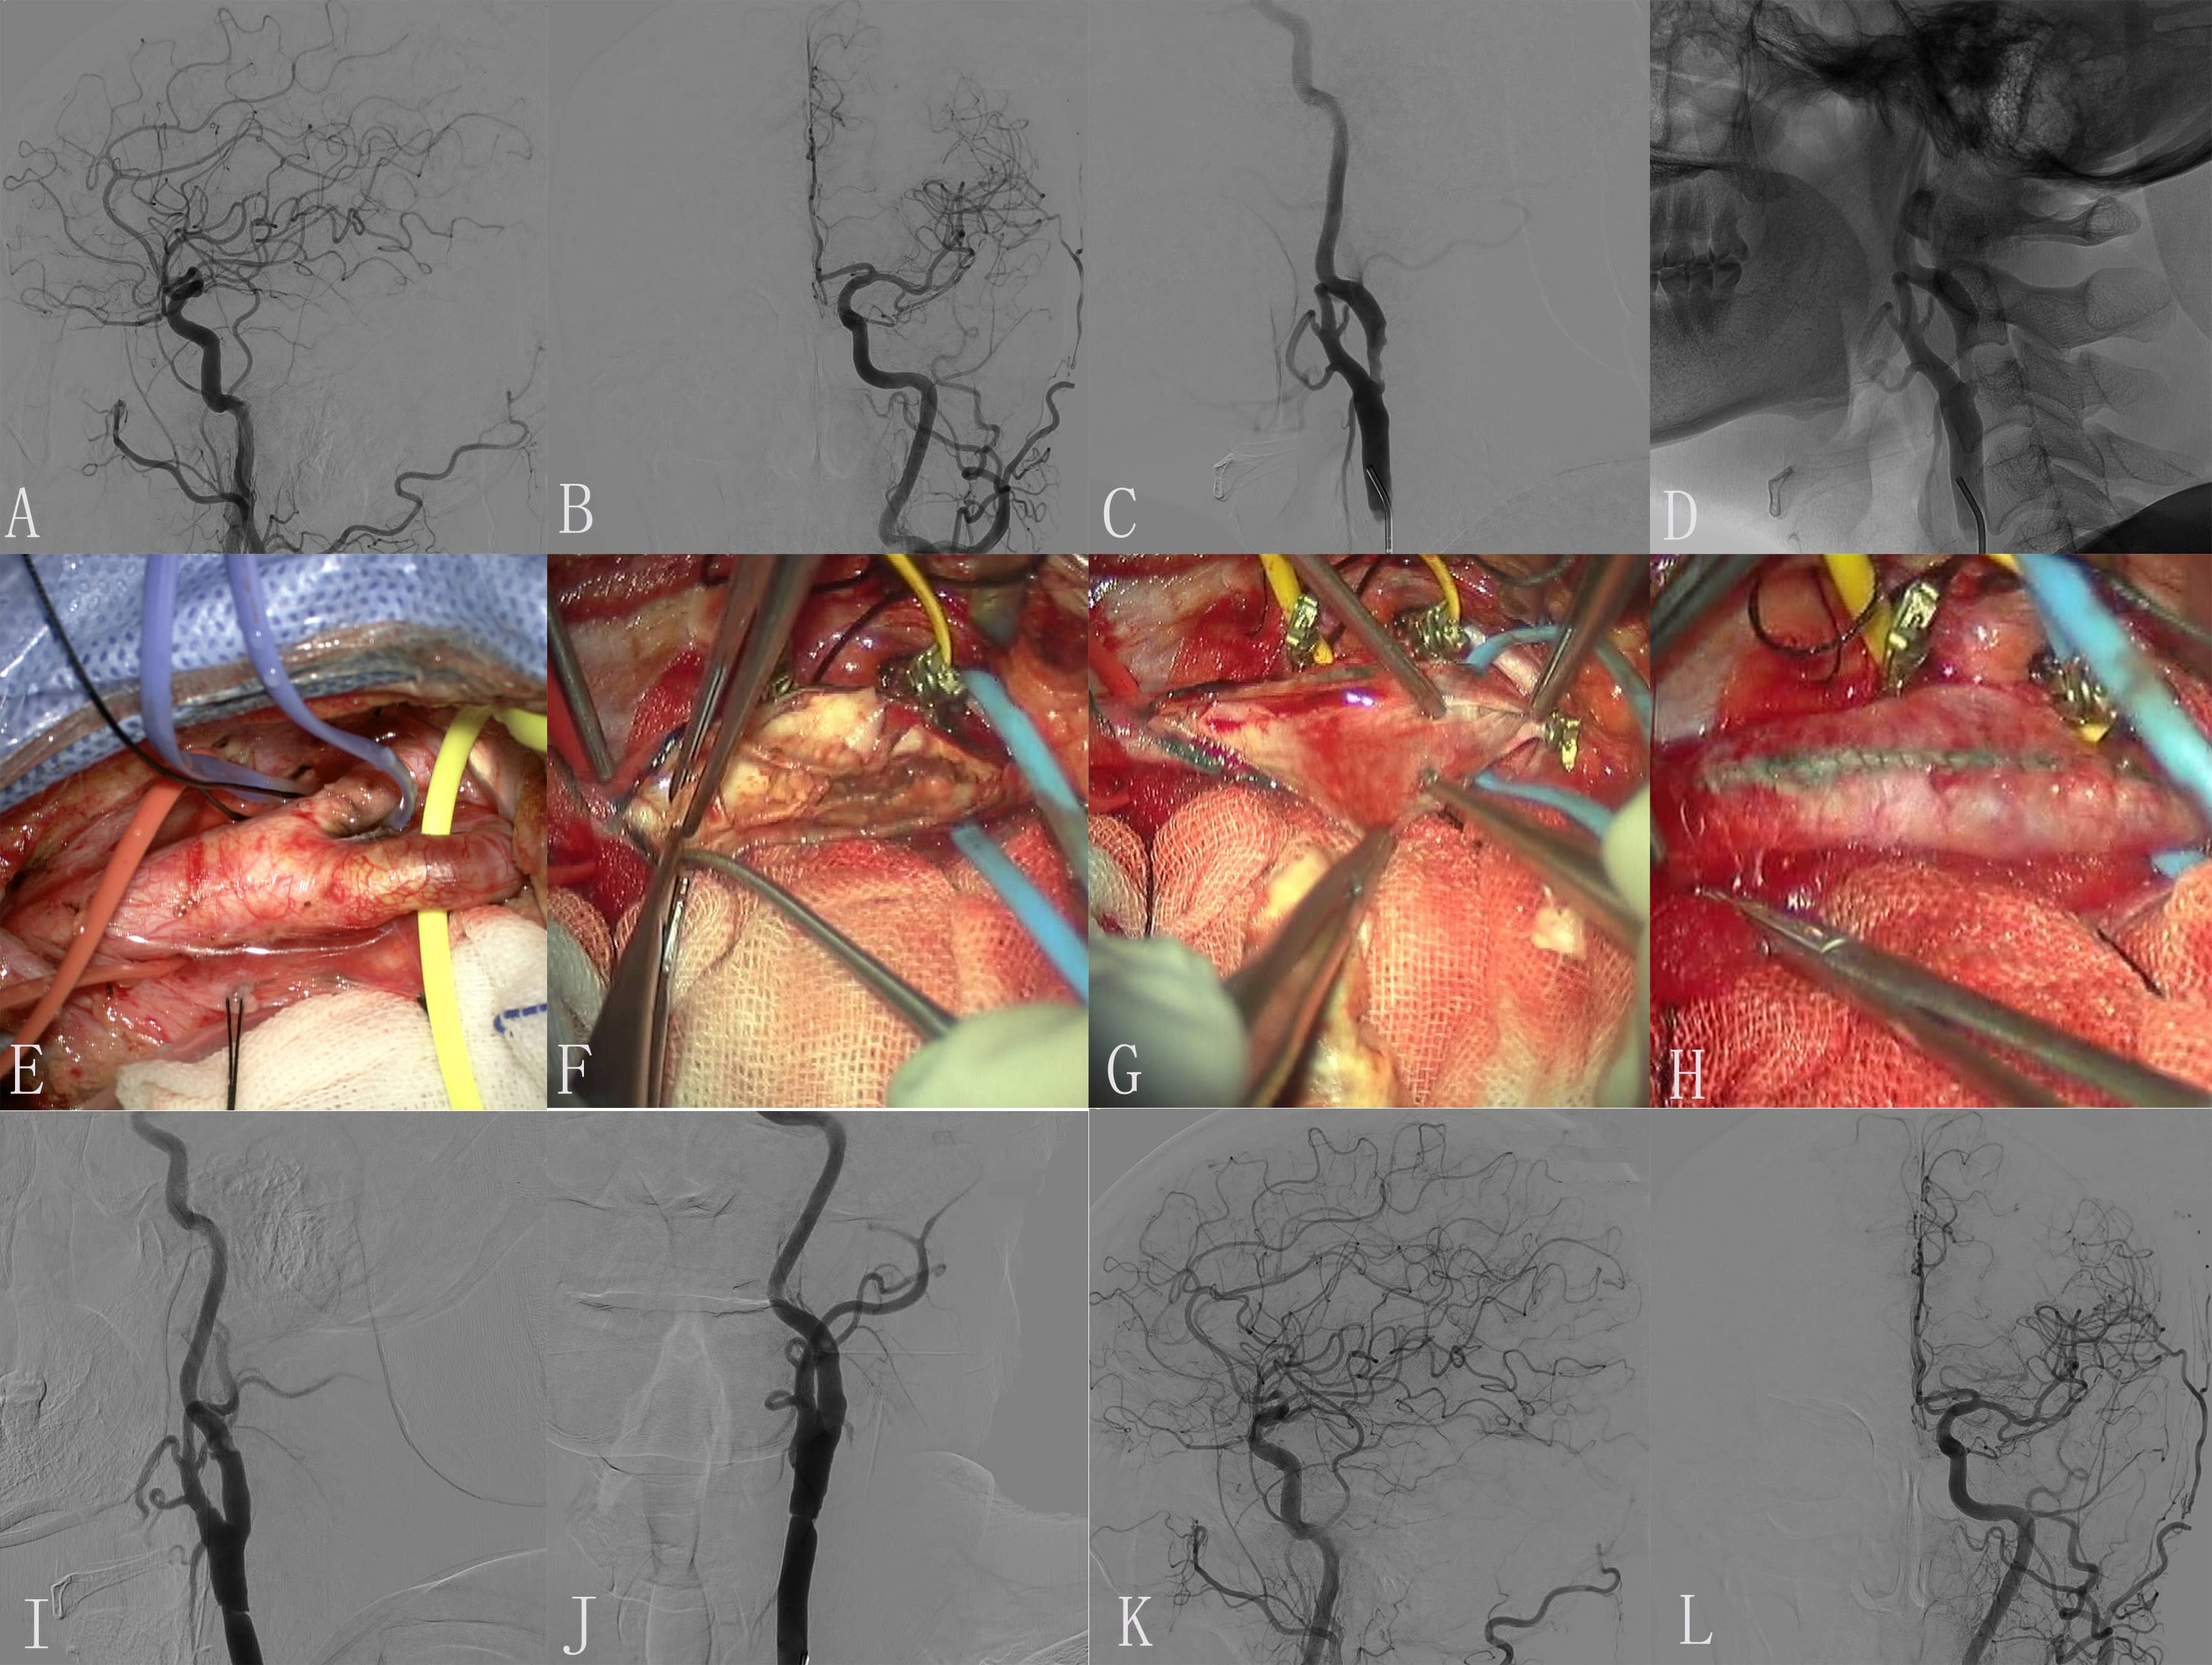

Fig. 1.Images of Case 1. (A) Preoperative right common carotid artery

(CCA) arteriogram revealed a severe proximal internal carotid artery (ICA)

stenosis. (B) Preoperative right middle cerebral artery (CMA) and anterior

cerebral artery (ACA) arteriogram revealed normal. (C) The endometrium of the CCA

was dissected longitudinally and presented as muddy unstable plaques. (D)

Completed removal of plaque. (E) Incision suture. (F) Close the carotid sheath.

(G) Intimal plaque. (H) Postoperative right CCA arteriogram revealed the M1

segment of the right MCA is occluded. (I,J) Superselective angiography of a

microcatheter through an occluded segment reveals a distal image of the occluded

vessel. (K,L) Solitaire 4

Fig. 2.Images of Case 2. (A,B) Preoperative left middle cerebral artery (MCA) and anterior cerebral artery (ACA) arteriogram revealed normal. (C,D) Preoperative left common carotid artery (CAA) arteriogram revealed a severe proximal internal carotid artery (ICA) stenosis. (E) Exposure of diseased vessel. (F) The endometrium of the CCA was dissected longitudinally and presented plaque. (G) Completed removal of plaque. (H) Incision suture. (I) Embolus was formed in carotid endarterectomy (CEA). (J) The thrombotic plaque disappeared after 0.5 mg tirofiban was administered to the artery. (K,L) Postoperative left ICA arteriogram revealed normal.